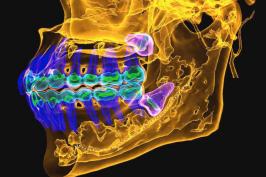

A raiz sumiu: dentes são reabsorvidos